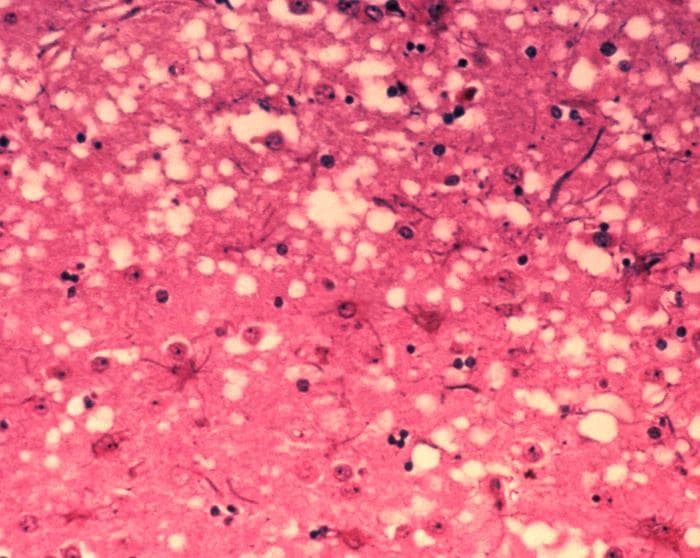

直到1980 年代,一位叫做普鲁希纳的人才证明:那不是细菌也不是病毒、而是一种折叠错误的蛋白质,会引发其他蛋白质也跟着折叠错误,最后使得动物的脑组织跟着孔洞化。普鲁希纳并把它命名为:「普利子」(Prion)。而这种物质引起最知名的疾病,就是1990 年代英国的狂牛症恐慌。

库鲁症会使动物的脑组织孔洞化,发展成海绵状的结构